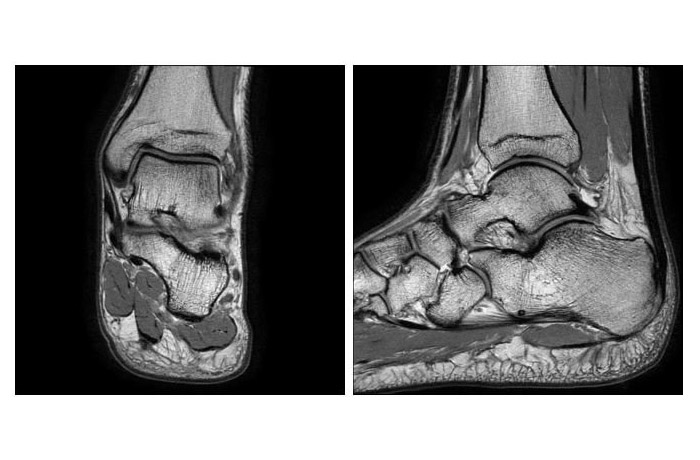

МРТ голеностопного сустава

МРТ голеностопного сустава является высокоточным методом диагностики травматических, анатомических, гистологических и дегенеративных изменениях сухожилий и связок и костей голеностопного сустава. Процедура позволяет с максимальной точностью и в разных проекциях визуализировать внутренние структуры, мышцы и кости стопы, что позволяет оценить состояние тканей голеностопа.